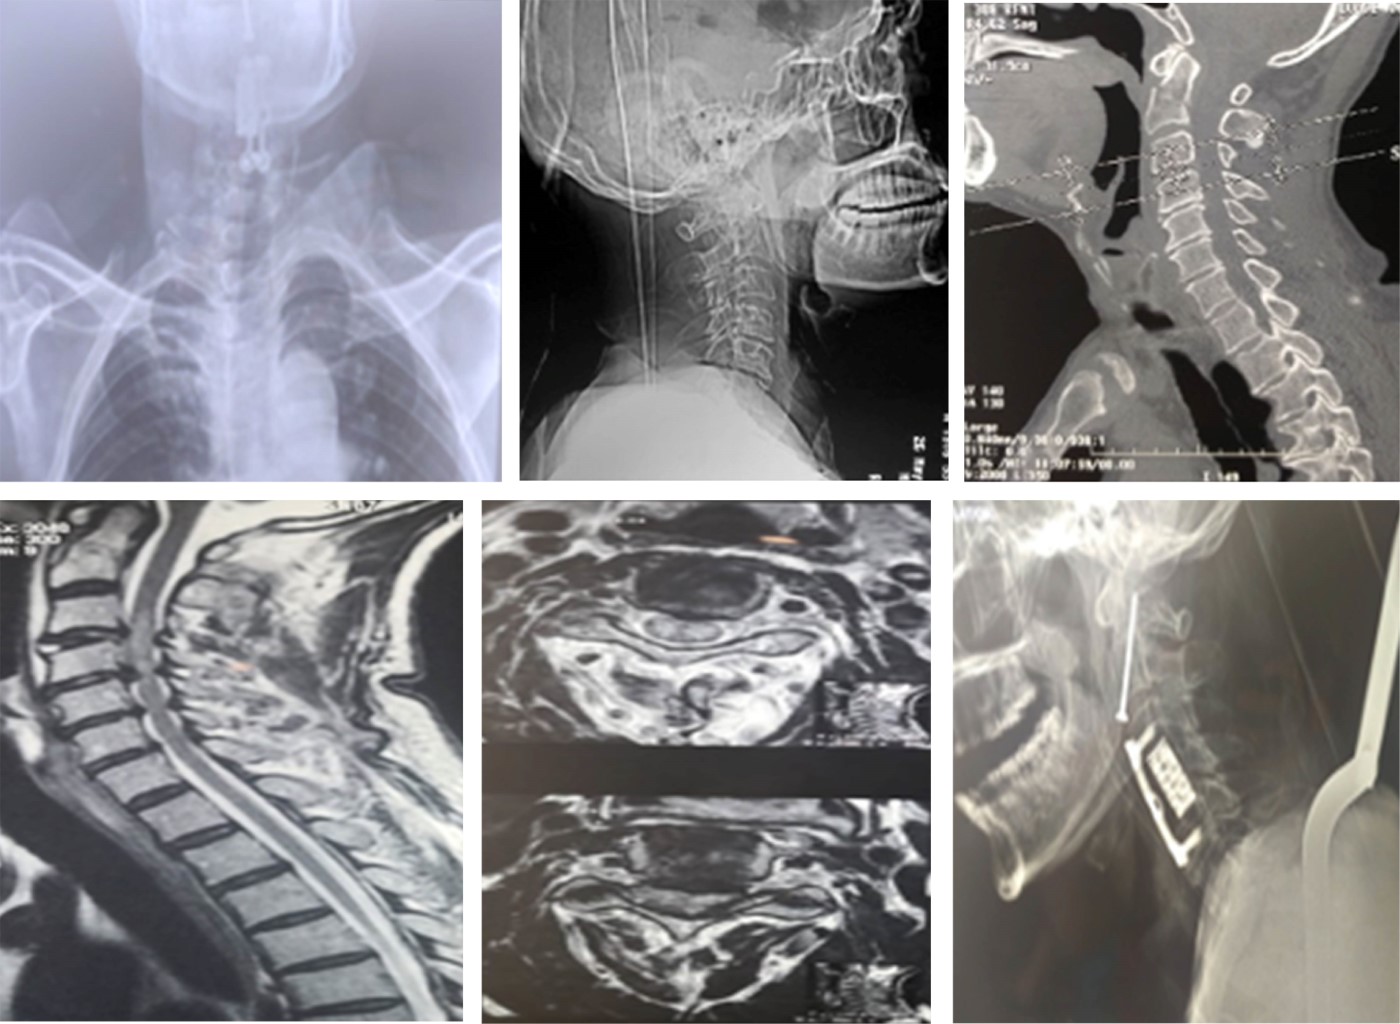

Con menos frecuencia el paciente puede tener lesiones asociadas a mielopatía cervical;6 en atención hospitalaria de primer contacto las radiografías son primordiales, se solicitan proyecciones cervicales anteroposterior, transoral, lateral, oblicuas y en ciertas indicaciones radiografías dinámicas en flexo-extensión. El estudio de imagen de elección es una tomografía axial computarizada (TAC) cervical, la cual proporciona la mejor resolución de los elementos óseos, lo que permite la identificación y clasificación de una fractura de apófisis odontoides. Si hay una lesión neurológica se debe obtener una resonancia magnética de columna cervical para lesiones asociadas, en algunos casos también pudiera llegar a solicitarse una angiotomografía.6

El tratamiento dependerá de la ubicación de la fractura de odontoides, según lo descrito por la clasificación de Anderson y D'Alonzo y los factores de riesgo del paciente para la falta de unión (la edad del paciente y sus comorbilidades) (Figuras 1 y 2).7 La osteosíntesis de las fracturas de la apófisis odontoides es un desafío debido a la anatomía y a las estructuras vecinas críticas que hacen que la fijación quirúrgica sea una tarea exigente.6,8

La cirugía fue el tratamiento primario en 20 pacientes (69%), con abordaje anterior en 37.93% (11 pacientes) y abordaje posterior en 31.03% (nueve pacientes). Por lo general, se prefirió la cirugía anterior en pacientes con líneas de fractura oblicua posterior u horizontal, dolor local y una superficie de contacto entre la odontoides y el cuerpo de C2. Se eligió un abordaje posterior cuando la distancia entre los fragmentos óseos fracturados fue > 2 mm, conminución o que existiera alguna asociación que requiriera estabilización posterior Se realizó un abordaje 360 (tornillo cervical anterior e instrumentación posterior) en un paciente (3.45%) que presentaba inestabilidad posterior además de una línea de fractura odontoidea horizontal.

El manejo para las fracturas de odontoides tipo II se puede dividir en dos grandes grupos, conservador y quirúrgico, este último se divide en dos abordajes en general.12 La primera opción es el abordaje anterior con la colocación de uno o dos tornillos odontoideos interfragmentarios, el cual se describe como la técnica de elección en la mayoría de las fracturas Anderson y D'Alonzo tipo II, siendo en específico los subtipos de acuerdo con la clasificación de Grauer IIA y IIB.13 El manejo quirúrgico con abordaje posterior se debe realizar de la mano con una reducción cerrada previa colocación de un halo cefálico y al igual que el tornillo odontoideo, control imagenológico transquirúrgico, realizando la instrumentación posterior C1-C2 dependiendo del tipo de trazo y el desplazamiento que se presente.14 Ambos abordajes son un recurso que, si bien cuenta con indicaciones específicas, es a elección del cirujano quien realizará un abordaje anterior o tras la valoración integral del paciente optará por un abordaje posterior al presentar algún dato de inestabilidad, o que tras la osteosíntesis anterior pudiera presentar una insuficiencia de la reducción y estabilidad.15,16

El abordaje posterior es utilizado principalmente cuando el desplazamiento del fragmento hacia anterior o posterior es mayor de 6 mm, presenta un desplazamiento mayor a 2 mm entre fragmentos o, cuando falla el tratamiento primario conservador o el tornillo odontoideo anterior.7,17 Estudios previos realizan el análisis de las tasas de seudoartrosis con una correlación estadísticamente confiable sólo con la edad de los pacientes.14 Ninguna otra característica de la técnica quirúrgica tuvo un impacto significativo en la tasa de seudoartrosis. Uno de los factores más importantes que se correlaciona con la tasa de complicaciones relacionadas con la osteosíntesis anterior y posterior es la habilidad y el nivel de experiencia del cirujano.7,18 La aplicación de navegación da como resultado una disminución de la exposición a la radiación y una precisión considerablemente mayor, por lo que la navegación es la alternativa adecuada para la fijación de la fractura odontoidea.14,19